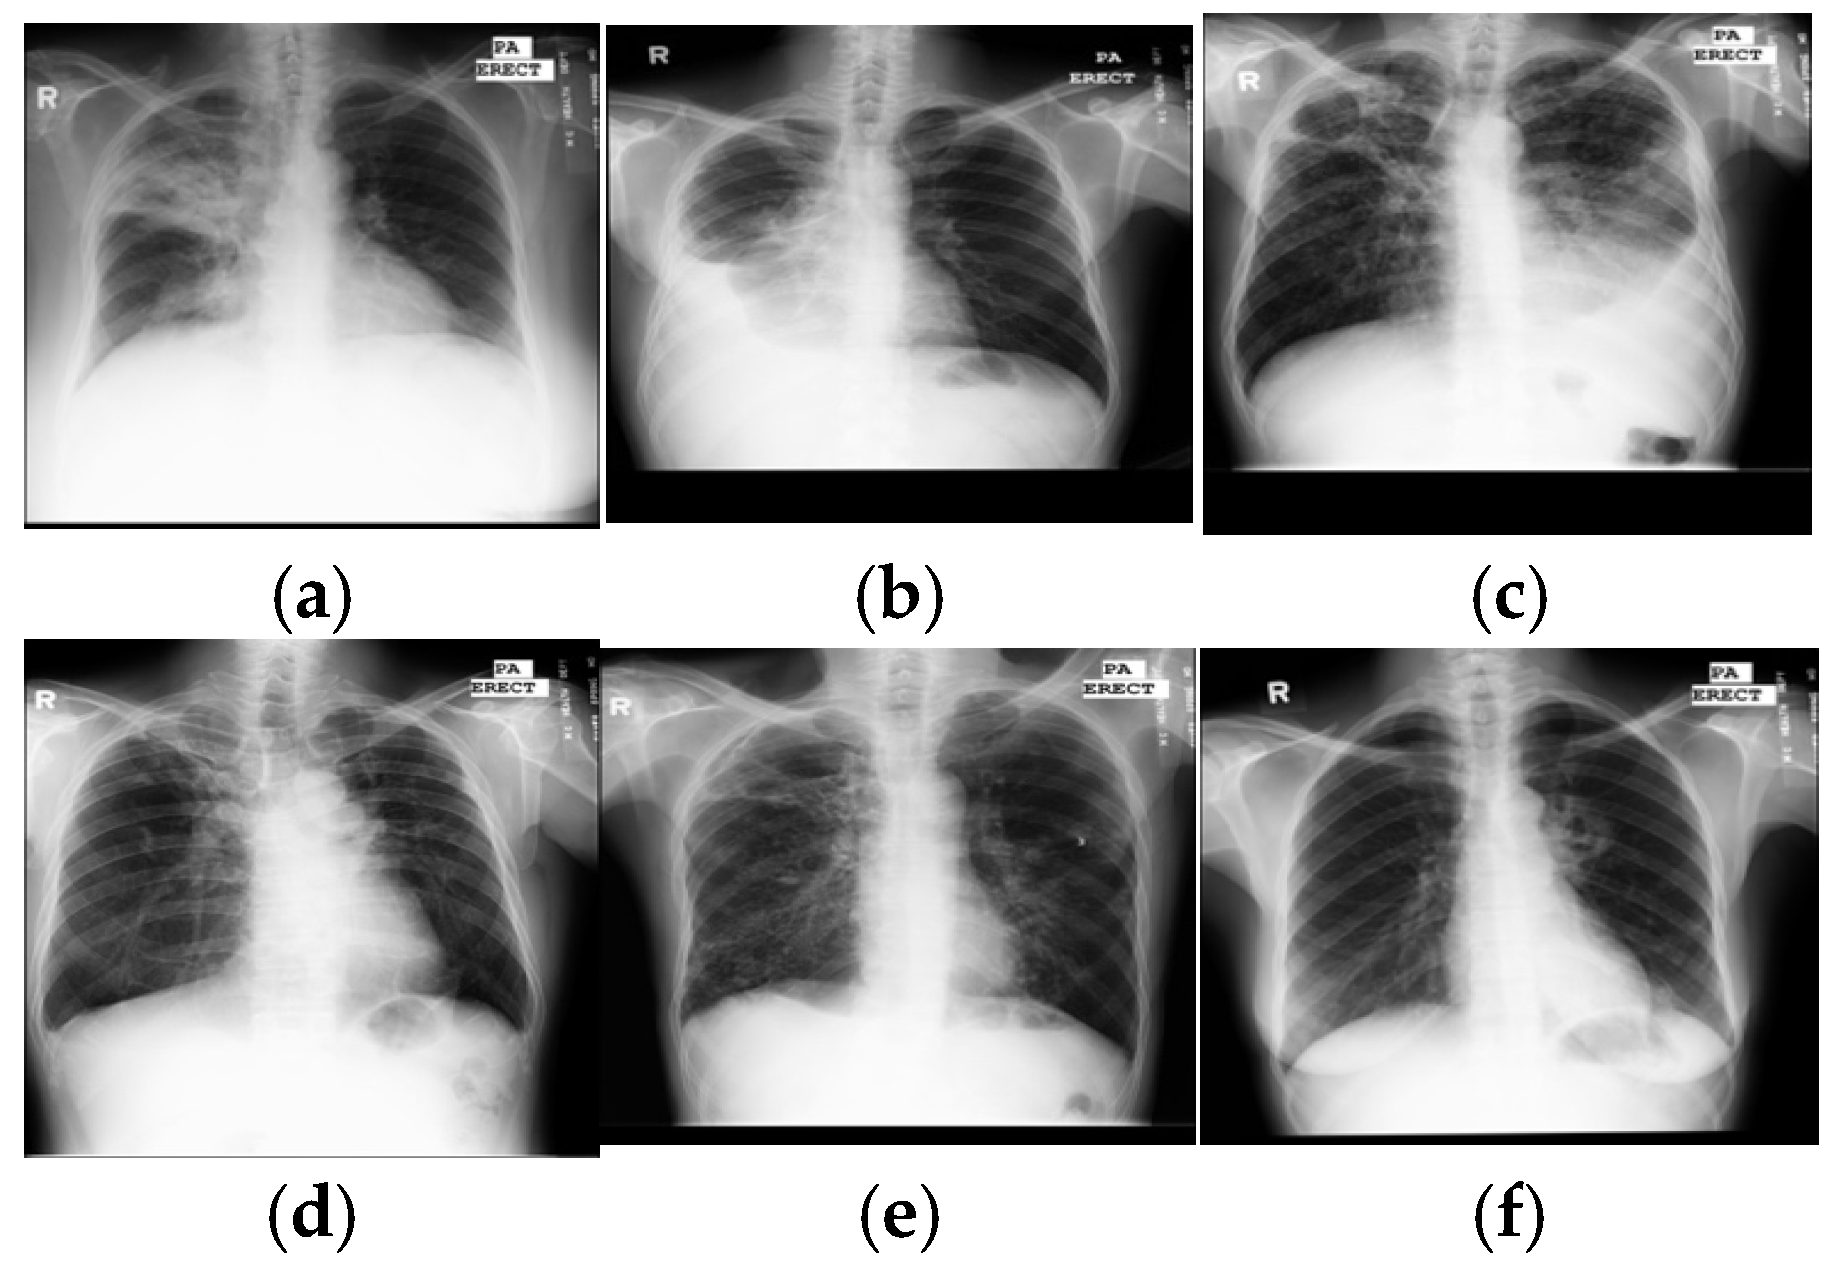

With rapid molecular analysis and bacteria culture methods, TB detection is now very accurate [2]. However, their limited availability and expense restrict widespread use in under-resourced countries with a high TB burden. Because they are not expensive and easily accessed, chest X-rays are mandatory for every evaluation of TB and become a critical screening, diagnostic, and triaging tool for TB and other lung diseases, including lung cancer, pneumonia, etc. A chest X-ray covers all thorax anatomical structures and is a high-yield test at a low cost from a single source. Common manifestations of TB, in X-ray images, are infiltrations, cavitations, consolidations, pleural effusion and thickening, opacities, miliary pattern, and nodules. Some typical TB lesions are shown in Figure 1. More examples of TB manifestations can be found in Daley et al.’s primer [3].

Figure 1. Samples of TB manifestations in X-ray images: (a) large infiltrate in RUL with cavitation and infiltrate in RML, (b) large right pleural effusion, (c) extensive infiltrates bilaterally with a large cavity in RUL and a moderate pleural effusion on the left, (d) TB scars, (e) cavitary disease RUL with possible small lobulated pneumothorax adjacent, with multiple coarse nodules in RLL as well as lesser amounts in LLL, and (f) cavitary infiltrate near left hilum consistent with TB in superior segment LLL. Key: RUL—right upper lung, RML—right middle lung, RLL—right lower lung, and LLL—left lower lung.